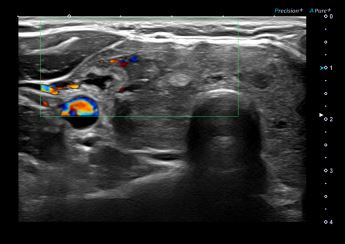

아산유외과개원후 146번째 갑상선암진단

상기환자 갑상선 추적관찰 중 이상소견으로 세침검사하신 30대 여성분으로

의심스러운 갑상선 우엽 검사 결과 갑상선암으로 진단되었습니다